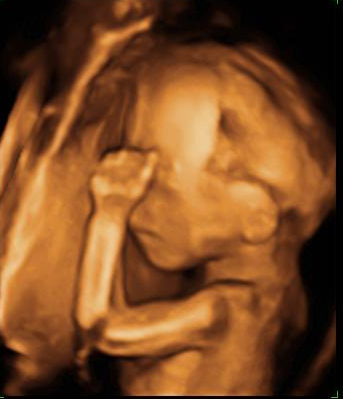

¡Estás en la semana 20 del desarrollo fetal, en la mitad del embarazo! Aquella diminuta célula hoy, 18 semanas más tarde, ya mide unos 20 centímetros y pesa casi un cuarto de kilo. Todos sus órganos vitales están formados, aunque todavía tienen que completar y perfeccionar su funcionamiento. En las próximas 20 semanas, el bebé dará "un estirón" espectacular: cuando nazca su longitud se habrá duplicado y su peso se habrá multiplicado por diez.

En esta semana, la embarazada tiene una cita ineludible con el médico: le harán una ecografía de alta resolución o ecografía morfológica. Se trata de una exploración muy minuciosa de la morfología del feto para descartar malformaciones.

Por ejemplo, se estudia que el corazón tenga las cuatro cavidades (dos aurículas y dos ventrículos), que los riñones, el hígado, el estómago y otros órganos se están formando correctamente.

Se cuentan las vértebras de la columna vertebral y los dedos de manos y pies (en ocasiones, cuando falta alguno es síntoma de otros problemas más graves).

Se observa que no hay fisuras del paladar, que el bebé tiene cristalino en sus ojos (aunque parezca mentira, es posible contemplar esta fina membrana que hace de lente), los huesos largos de brazos y piernas.

Se calcula la circunferencia del abdomen y la circunferencia cefálica, y estos datos permite saber los percentiles fetales y si el crecimiento fetal es armónico y se corresponde con su "edad gestacional".

"La ecografía de la semana 20 es una de las más importantes del embarazo, porque el bebé ya es lo suficientemente grande como para poder observar todos sus órganos con claridad y evaluar su desarrollo. Estos ya están formados y es posible verlos. Se hace un repaso anatómico del feto y medimos sus huesos para evaluar su crecimiento. De esta forma, descartamos malformaciones importantes".

Dra. Teresa Izquierdo, Unidad de Diagnóstico Fetal y Ecografía del Hospital Vithas 9 de Octubre, en Valencia.